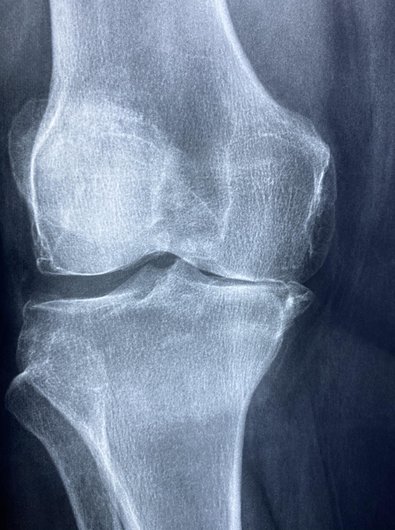

특히 연골은 관절의 충격을 흡수하고 마찰을 줄여주는 역할을 하는데, 한번 손상되면 재생이 어렵기 때문에 미리 관리하는 것이 매우 중요합니다.

셋째, '관절을 움직이기 힘들거나', '관절의 운동 범위가 현저히 감소'했을 때도 위험 신호입니다.

이는 연골 손상이나 심각한 관절 질환의 징후일 수 있습니다.